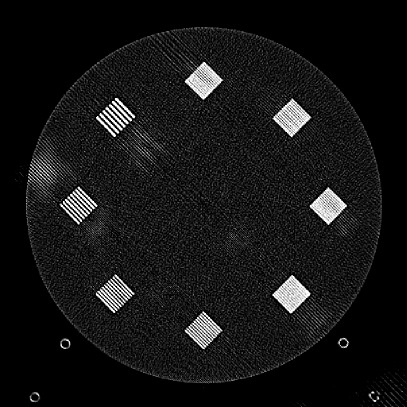

To evaluate image quality, we first tested the performance of JENG on a standard CT phantom, CT ACR 464 phantom 35. Then we tested JENG on 5 clinical thoracic datasets and 3 abdominal datasets. The ACR 464 phantom contains four modules in total, with each module 40 mm in depth and 200 mm in diameter. The first module has 4 different inserts to test CT number fidelity. In addition, the module contains a series of wires for cross-plane resolution evaluation, shown as white horizontal bars near the center in Fig. 9(a), and are visible in 0.5 mm z-axis increments. The second module tests low contrast resolution, but is not used in this paper. The third module, shown in Fig. 9(b), is a uniform cylinder of water-equivalent material of 0 Hounsfield units (HU), and we used this module to quantitatively measure image noise profile and in-plane resolution. The fourth module consists of resolution bars of various spatial frequencies for analysis on high contrast resolution. To scan the phantom, the scanner setup used dual sources with 2 focal spots at each source. In addition, the projections were acquired using the same protocol for clinical thoracic scans with 100 KV, a nominal tube current of 718 mA and a high helical pitch of 2.8. For all experiments, we compared JENG against the state-of-the-art Siemens ADMIRE, reconstructed with a BL-64 soft tissue sharp kernel, and we define ADMIRE as the clinical standard hybrid IR method for the rest of the paper.

Figure 10: Clinical Standard hybrid IR vs JENG performance, with a display window center of 650 HU and a window width of 1500 HU. The spatial frequencies for bar patterns from top going clock-wise are 1.2, 1.0, 0.9, 0.8, 0.7, 0.6, 0.5, 0.4 mm-1. (a) The clinical Standard hybrid IR at L1 denoising strength using a soft tissue high contrast kernel. Note that significant aliasing streaking artifacts are present near the bar patterns. (b) JENG at a comparable L1 noise level but with much clearer bar pattern and fewer artifacts than the clinical standard hybrid IR. (c) The clinical standard hybrid IR at a stronger denoising strength of L3. (d) JENG at a comparable L3 noise level.

The first experiment we performed was a visual comparison of in-plane spatial resolution between JENG and the clinical standard hybrid IR. We used the ACR phantom module 4 for this evaluation, which has 8 resolution bars of various spatial frequencies from 0.4 mm-1 to 1.2 mm-1. To obtain a fair comparison, we matched the image noise variance in the uniform regions of JENG and the clinical standard hybrid IR and studied their in-plane spatial resolution and undersampling streaking artifacts. In addition, we performed two sets of experiments. The first set of experiments matched their image noise variance at the L1 denoising strength of the clinical standard method with a noise variance of 33926 in the uniform regions. The second set of experiments matched their image noise variance at stronger L3 denoising strength of the clinical standard method with a noise variance of 12988 in the uniform regions.

Fig. 10 is an example image for resolution bars and the spatial frequencies for the bar patterns from top going clockwise are 1.2, 1.0, 0.9, 0.8, 0.7, 0.6, 0.5 and 0.4 mm-1. Fig. 10(a) is the resolution bars reconstructed by the clinical standard hybrid IR at L1 denoising strength. Fig. 10(b) is JENG reconstructed at an image noise variance comparable to the L1 denoising. Fig. 10(c) is the clinical standard hybrid IR at a stronger L3 denoising strength and we can observe that the result at L3 denoising leads to less image noise than the result at L1 denoising in Fig. 10(a). Fig. 10(d) is JENG at an image noise variance comparable to the L3 denoising. To help readers better see the image quality difference between the clinical standard hybrid IR and JENG, Fig. 11 is the difference image between the two algorithms at L1 denoising. A noticeable difference between the clinical standard hybrid IR and JENG is that the clinical standard method in Figs. 10(a) and (c) have strong undersampling aliasing artifacts near the phantom periphery, which show a pattern of high density streakings and the streakings point along the direction of X-rays. In addition, the magnified sub-figures show that the bar pattern at 0.8 cycles/mm is unresolved with blurry details. In contrast, JENG in Figs. 10(b) and (d) effectively decimates the undersampling artifacts and the bar pattern in the magnified sub-figures of JENG is completely resolved with clearer details.